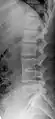

Block vertebrae

Block vertebrae occur when there is improper segmentation of the vertebrae, leading to parts of or the entire vertebrae being fused. The adjacent vertebrae fuse through their intervertebral discs and also through other intervertebral joints so that it can lead to blocking or stretching of the exiting nerve roots from that segment. It may lead to certain neurological problems depending on the severity of the block. It can increase stress on the inferior and the superior intervertebral joints. It can lead to an abnormal angle in the spine, there are certain syndromes associated with block vertebrae; for example, Klippel–Feil syndrome. The sacrum is a normal block vertebra.